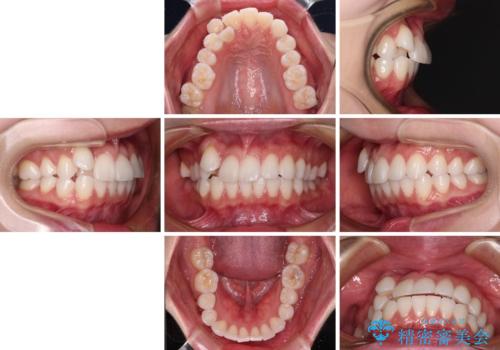

- 八重歯と、それによる正中のズレを気にして来院された患者様です。

口元の突出感は気にしていなかったため、上顎の左右第一小臼歯を抜歯することで、八重歯の解消と上顎の正中を改善していくこととしました。

奥歯の咬み合わせを維持しながら正中位置を改善するために、補助装置を使用しました。

予定より期間がかかりましたが、上下の正中位置を綺麗に一致させることができました。